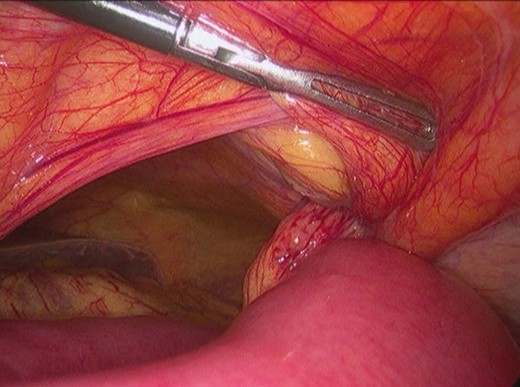

The patient underwent an urgent laparoscopy which showed small bowel herniating through the defect in the left posterior rectus sheath located above the arcuate line (Fig. 4). The hernia was reduced and the defect was repaired laparoscopically with polypropylene/PTFE mesh (Figs 5 and 6). The incarcerated segment of small bowel was edematous with a stenotic and ischemic area and therefore was resected through a small periumbilical incision. The procedure was performed with three incisions (two in rights quadrants and one in umbilical area) (Fig. 7).

Surgery—laparoscopic mesh repair with polypropylene/PTFE mesh.